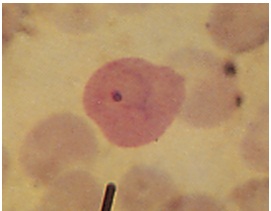

Plasmodium Morphology

Plasmodium

Trophozoit Plasmodium falciparum:

Trophozoit Plasmodiumvivax: